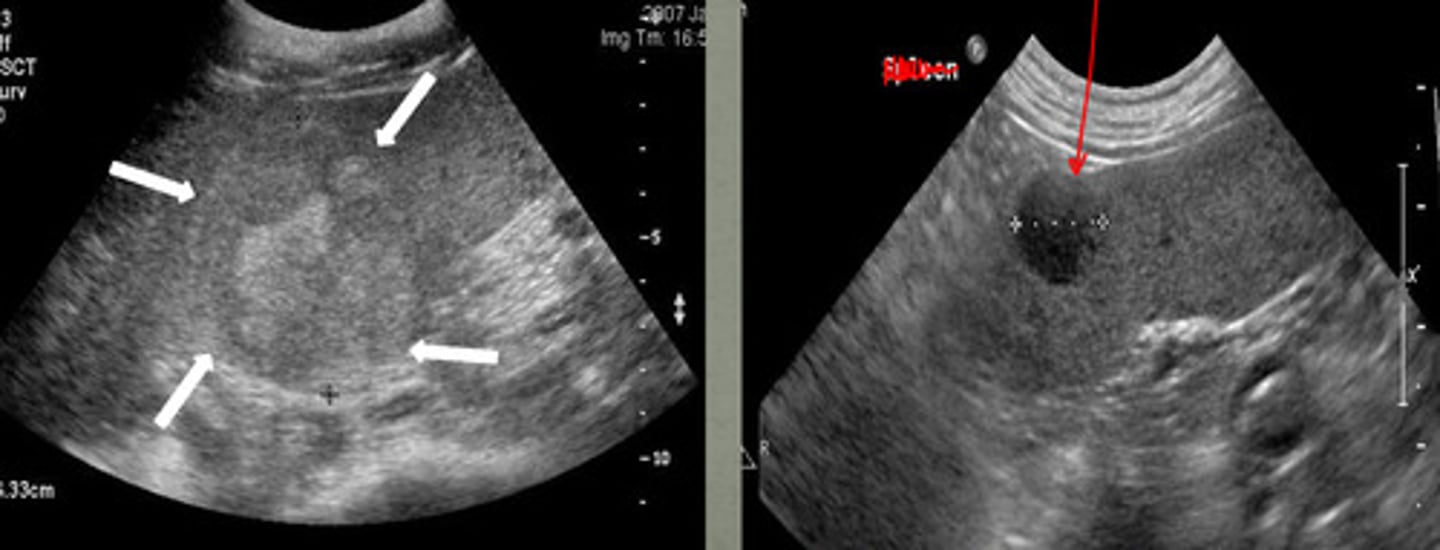

right- there is a mass on the ventral side

which of these US images of the liver is abnormal?

diaphragm

what is the red arrow pointing to in the left image?